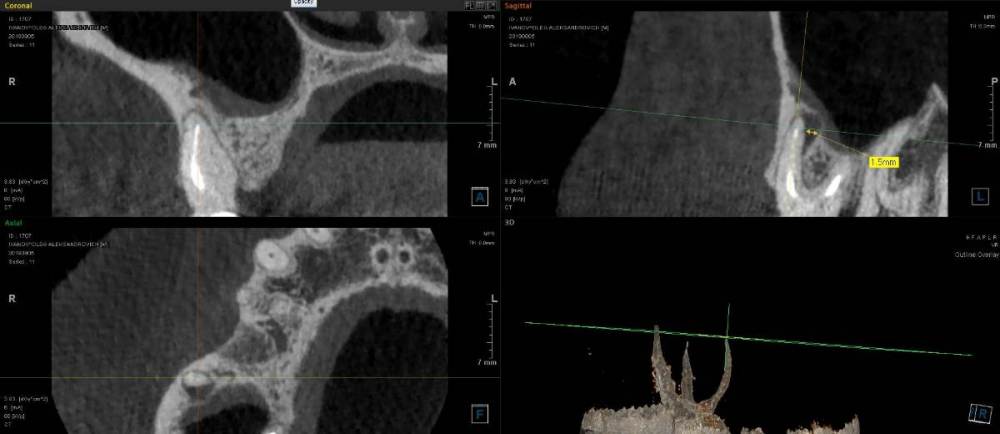

ict Опубликовано 27 мая, 2022 Автор Поделиться Опубликовано 27 мая, 2022 для истории. Через полгода появился свищ у проблемного канала. Перед резекцией верхушки корня хирург попросил перепломбировать канал. думаю перепломбировать не было смысла до конца все равно 0.9мм не смогли пройти, но и вреда не было - верхушка спиливалась, пломбу высверлили в центре и пломба полностью не снималась. Думаю верхушка с канальцами и сгнила. На КТ (справа внизу) при выборе отображения плотности видно, что у верхушки на 1.7мм есть ступенька с меньшей твердостью (декальцинирован) Ссылка на комментарий